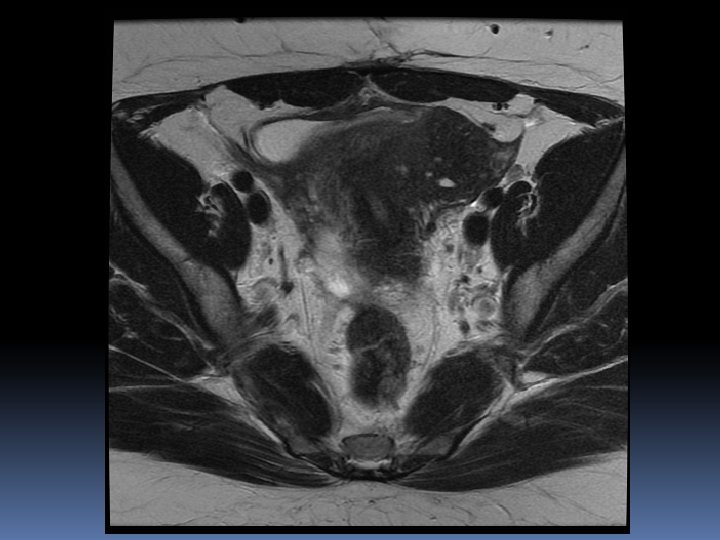

Endometriomi, molteplicità e “dark spots” in T 2 Endometriomi bilaterali, kissing ovaries